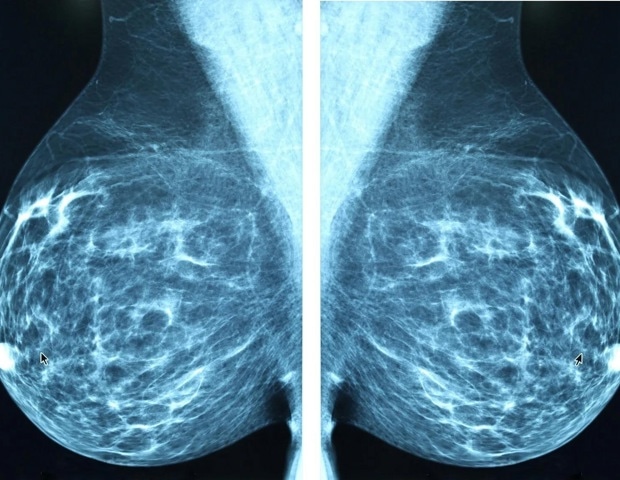

Наиболее распространенной и смертельной формой этого заболевания у женщин после менопаузы является рак молочной железы, положительный по рецептору эстрогена (ER+). По словам Джойс Слингерланд, доктора медицинских наук, которая является одним из руководителей программы взаимодействия с раком в Комплексном онкологическом центре Ломбарди Джорджтаунского университета, перспективы ER-позитивного рака молочной железы особенно суровы для женщин в постменопаузе с ожирением: у них чаще диагностируется эта форма заболевания, и они в 2-3 раза чаще умирают от него.

Это особенно тревожно, поскольку, по оценкам, к концу десятилетия ожирение затронет почти половину женщин в Соединенных Штатах».